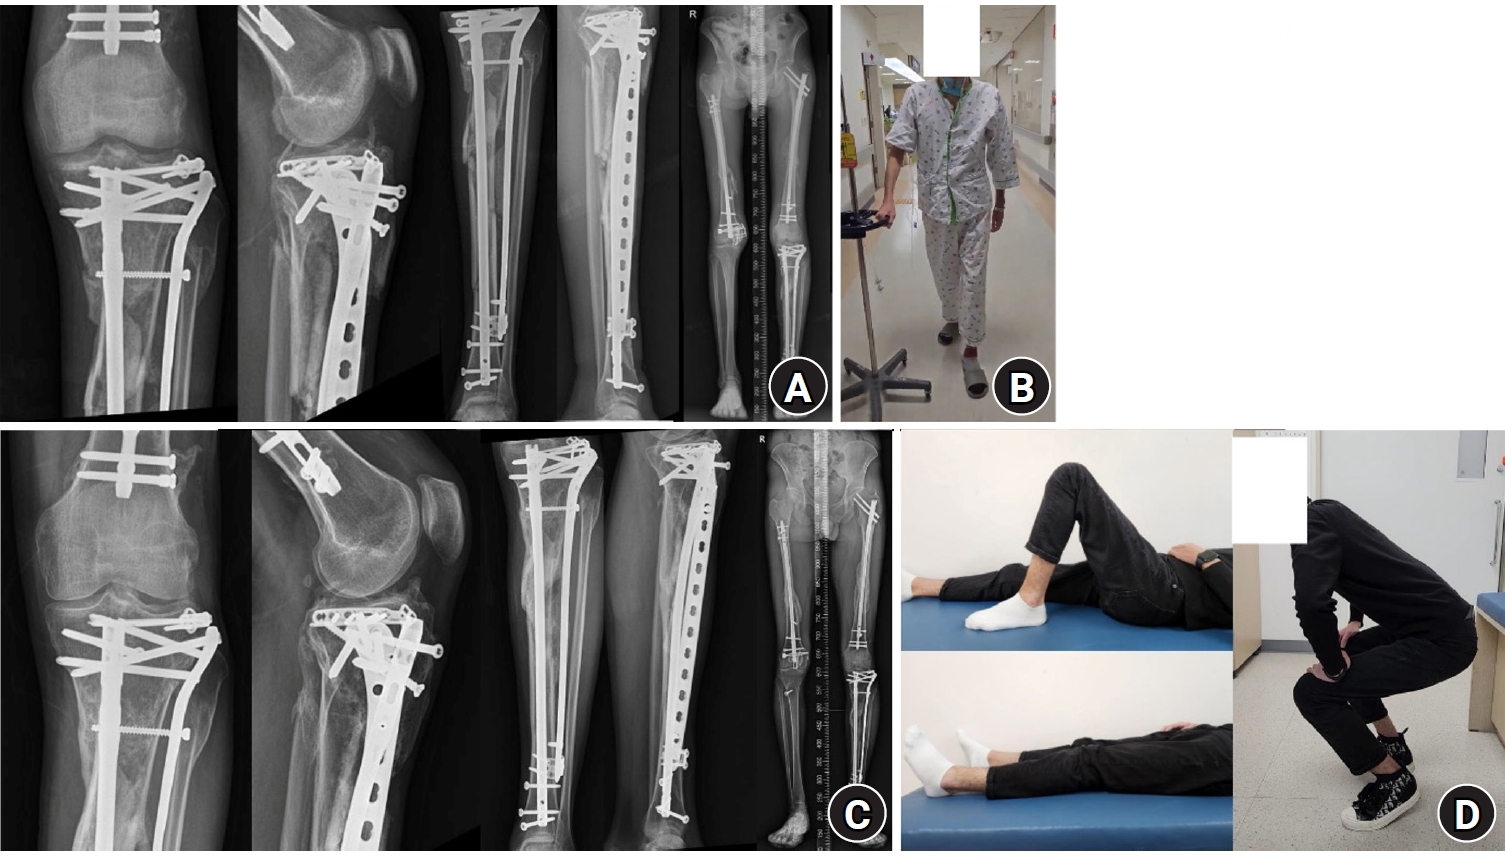

Fig. 4.

Follow-up plain radiographs and clinical photographs taken 6 weeks and 1 year after surgery. (A) Plain radiographs 6 weeks postoperatively. (B) Clinical photograph showing the patient ambulating with a walker 6 weeks after surgery. (C) Plain radiographs taken 1 year postoperatively. (D) Clinical photographs 1 year after surgery showing good knee joint range-of-motion and the ability to perform squatting exercises.

Knee joint range-of-motion exercises were initiated immediately after surgery. Two weeks after surgery, the right tibial anteromedial open wounds had healed without complication. Assisted ambulation began 4 weeks after surgery, and by 6 weeks, the patient could ambulate independently with a walker, and fracture reduction was sustained in both lower limbs (Fig. 4A and 4B). Complete bone union was achieved for all fractures 6 months after surgery. The early initiation of rehabilitation helped the patient regain the ability to perform daily living activities, and at the 1-year follow-up, full functional recovery was confirmed (Fig. 4C and 4D).